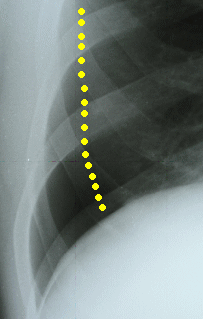

肺がしぼんでいる。

点線。

33歳 男性の気胸。

右胸の痛みで発見。